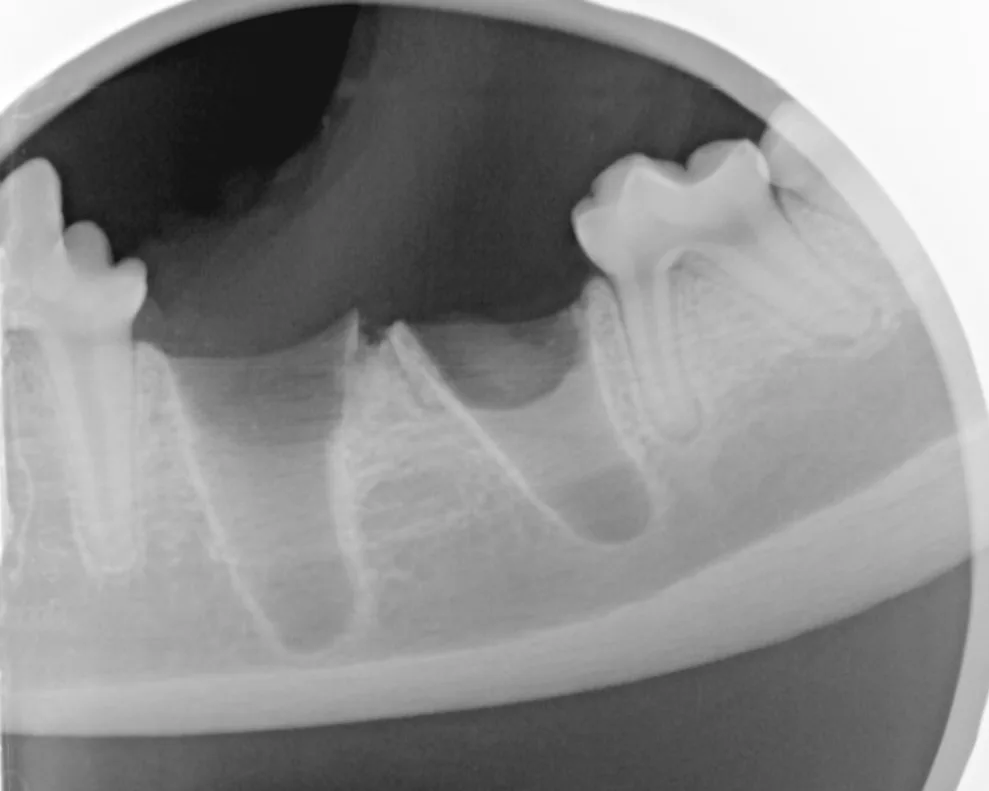

Obtain a postoperative radiograph to verify that the entire tooth was extracted, and document the condition of the mandible following the extraction.